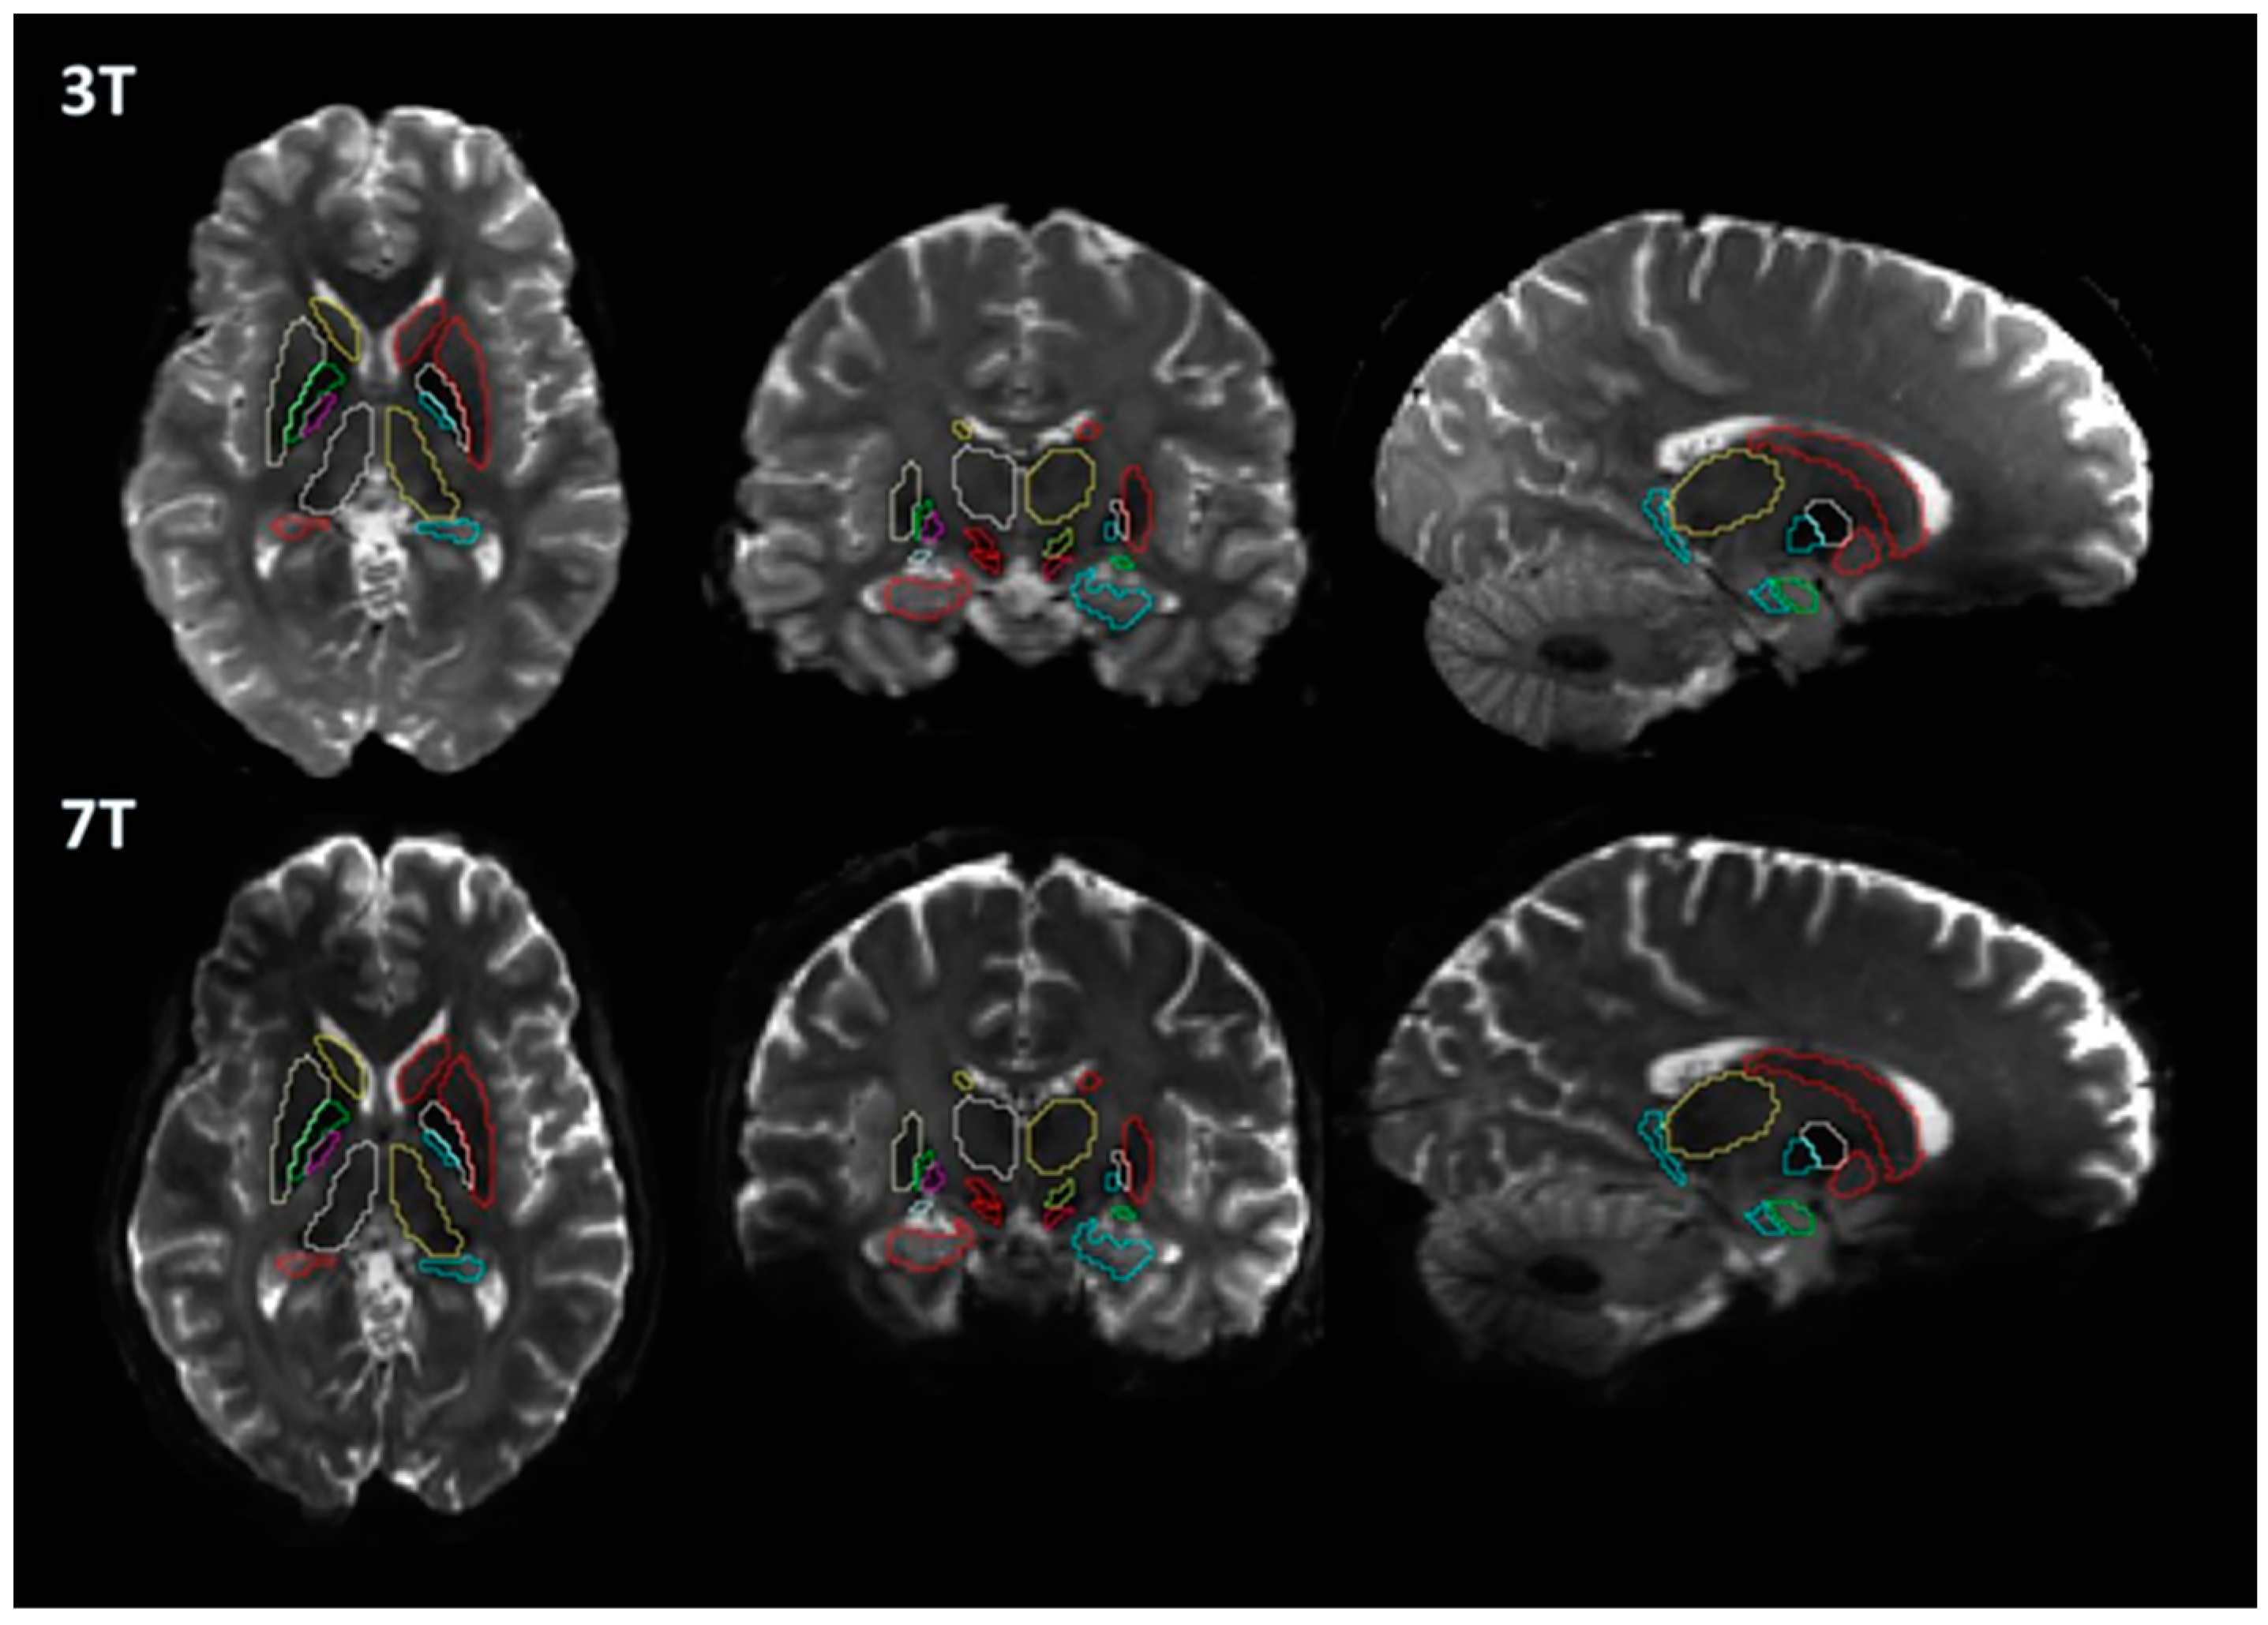

2.3. Image Processing

3. Results